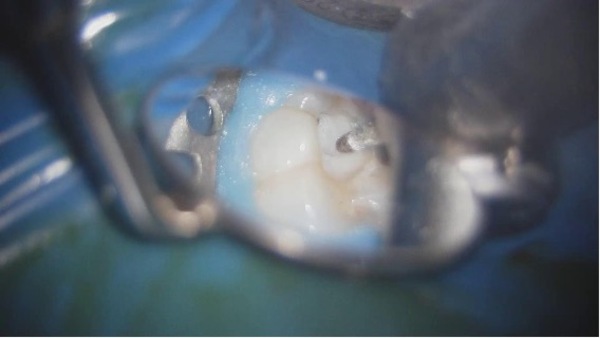

実際に治療を進めていく様子です。

マイクロスコープ下で昔の詰め物を除去していきます。

通常の方法で、根管治療を行います。